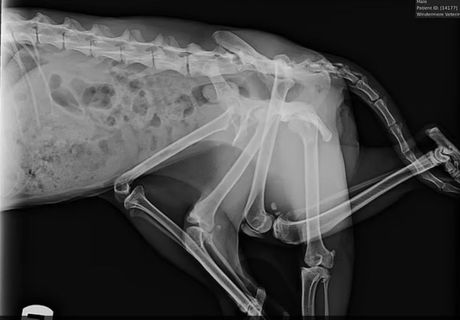

Mačka sa šest nogu Foto: Furget Me Not Animal Rescue

U Windermere veterinarskoj bolnici, stručni tim proveo je dva sata u operacionoj sali. Uklonjene su dve dodatne noge, kao i jedna zdrava zadnja noga, jer su sve bile spojene preko nepotpune karlice koju organizam nije uspeo da apsorbuje tokom razvoja.